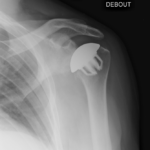

Le but de la prothèse de l’épaule est d’enlever les zones d’os et de cartilage qui sont usées, et de les remplacer par des pièces artificielles ayant les mêmes formes.